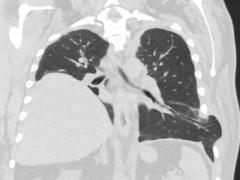

Een vrouw met pulmonale klachten na re-spondylodese